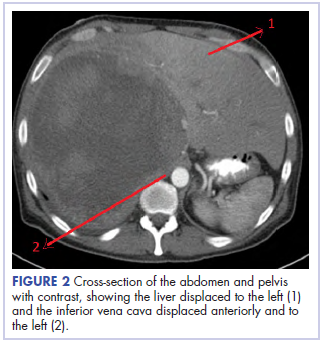

Before confirmatory pathologic evaluation could be completed, the patient presented to his local hospital again in excruciating pain. A CT scan of his abdomen and pelvis demonstrated a massive subacute on chronic hematoma in the right retroperitoneum measuring 22 × 19 × 18 cm, with calcifications originating from an upper pole right renal neoplasm. The right kidney was displaced antero-inferiorly, and the inferior vena cava was displaced anteriorly and to the left. The preliminary pathology returned with findings suggestive of sarcoma (Figures 1 and 2).